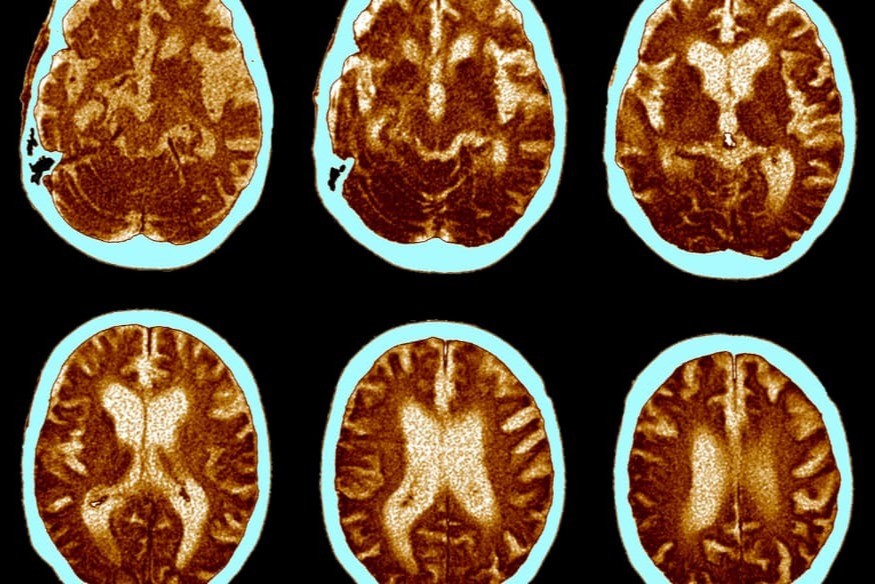

Une étude clinique randomisée en double aveugle menée sur 60 hommes atteints de troubles bipolaires montre qu'une supplémentation quotidienne de 2 g d'oméga-3 pendant deux mois augmente significativement les niveaux sériques de BDNF, facteur neurotrophique dérivé du cerveau, et réduit les scores de dépression selon l’échelle d’évaluation de Hamilton. Comparée au placebo, l’intervention a permis une hausse du BDNF de 0,504 à 0,756 ng/mL et une baisse des scores de dépression de 29,35 à 22,40. Ces résultats confirment l’intérêt potentiel......